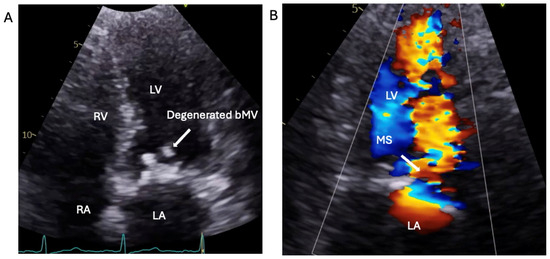

1.1.3. Case 3

2.3. The Saga of Relapsing IE of the Prosthetic Mitral Valve Causing Structural Valve Degeneration and Transcutaneous MViV Prosthesis